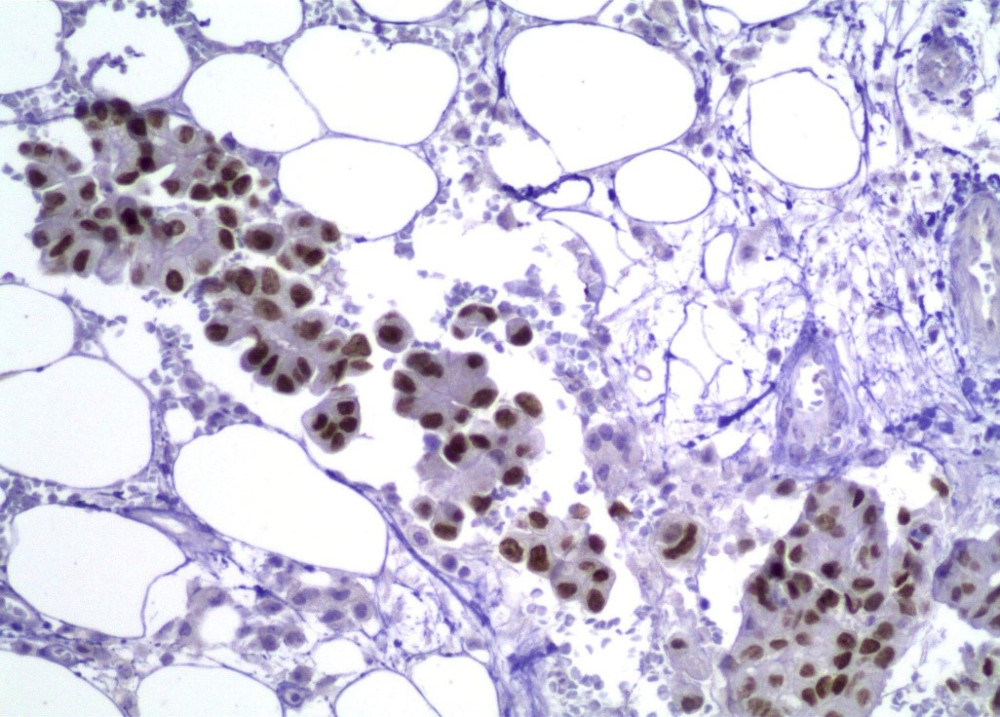

Acude con médico quien solicita Rx de tórax, identificando una lesión parahiliar derecha. Se toma biopsia por punción (FOTOS 1 Y 2)

Figura 2

RESULTADOS DE INMUNOHISTOQUÍMICA:

TTF-1

NAPSIN-A

Adenocarcinoma invasor, predominantemente acinar con áreas micropapilares, no mucoproductor primario de pulmón, con extensión a pleura y tejidos blandos.